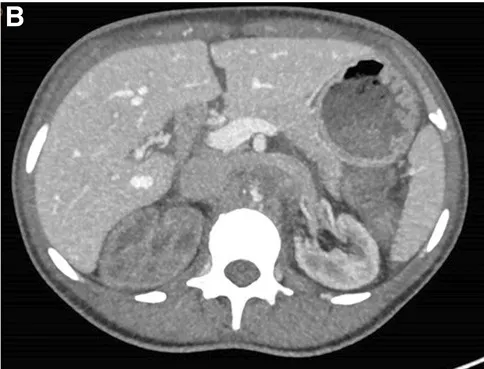

Realizado USG renal com Doppler que mostrou ecogenicidade e tamanho renal normais, mas sinais de oclusão aórtica na emergência da artéria mesentérica superior, o que foi confirmado por tomografia computadorizada com contraste (Figura 1).

A TC também revelou importante circulação colateral na parede abdominal, permitindo suprimento sanguíneo suficiente para os membros inferiores. Apenas o rim esquerdo mostrou captação residual de contraste (Figura 1), sugerindo rim direito isquêmico.

TC com contraste (reconstrução 3D) mostrando oclusão aguda da aorta justa-superior da artéria mesentérica. (A) Oclusão aórtica justa-superior à artéria mesentérica (marcada com um ⊗) juntamente com vasos colaterais na parede abdominal (B) Rim esquerdo com realce de contraste e rim direito sem realce sugerindo falta de perfusão renal.